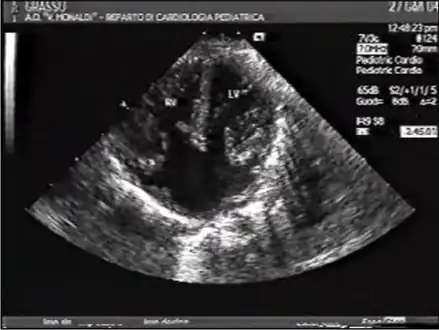

Ultrasound showing a complete atrioventricular septal defect

AVSDs can be detected by cardiac auscultation; they cause atypical murmurs and loud heart tones. Confirmation of findings from cardiac auscultation can be obtained with a cardiac ultrasound (echocardiography - less invasive) and cardiac catheterization (more invasive).

Tentative diagnosis can also be made in utero via fetal echocardiogram. An AVSD diagnosis made before birth is a marker for Down syndrome, although other signs and further testing are required before any definitive confirmation of either can be made.